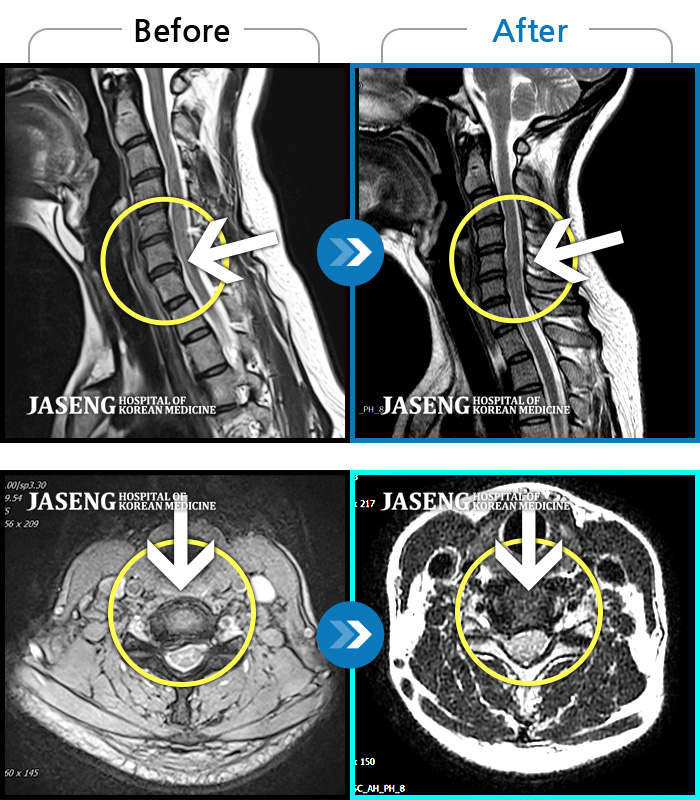

목디스크

도움받은 사례

인천 · 강아현 원장

처음 내원시 목에서 등으로 이어지는 통증 및 우측 팔 저림 증상이 심했고, 약간의 근력저하도 동반되어 일상생활이 어려운 상태였습니다.

촬영시기

2024.04.06 ~ 2024.11.16

2024.11.22

조회수 17,045